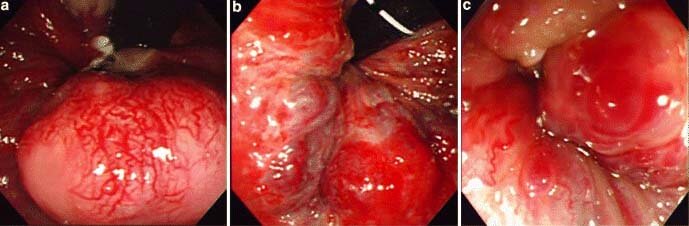

Cách chữa bệnh trĩ nội bằng kĩ thuật PPH

Đây là cách chữa bệnh trĩ nội hiệu quả hiện nay áp dụng với các tình trạng bệnh trĩ nội ở giai đoạn nặng cấp độ 3-4 (còn gọi là kỹ thuật “Thắt vùng niêm mạc trĩ”).

Kỹ thuật không làm tổn hại tới chức năng sinh lý của lớp đệm hậu môn, rút ngắn thời gian tiểu phẫu và giảm đau một cách rõ rệt.

Là kỹ thuật tiên tiến được phát triển trên cơ sở học thuyết về lớp đệm hậu môn và vận dụng máy ôn hợp để cắt trĩ dạng vòng.

Ưu điểm của kĩ thuật PPH

- An toàn: Không cần cắt bỏ lớp đệm hậu môn, bảo vệ chức năng hậu môn tới mức tối đa, tránh được các biến chứng hẹp hậu môn, mất kiểm soát hậu môn…

- Không đau: Đưa búi trĩ bị sa về vị trí ban đầu, đồng thời cắt đứt đường cung cấp máu cho búi trĩ, không làm tổn thương bề mặt ống hậu môn, sau thủ thuật gần như không cảm thấy đau.

- Vết thương nhỏ, nhanh hồi phục: Điều trị cắt vòng niêm mạc không cần dùng dao mổ, mất máu ít, không lo phải thay thuốc sau tiểu phẫu và nhanh chóng về sinh hoạt bình thường.

- Áp dụng nhiều đối tượng: Do ít gây tổn thương nên đặc biệt thích hợp với nhiều đối tượng bệnh nhân, hoặc người bệnh bị tái phát do dùng phương pháp truyền thống…